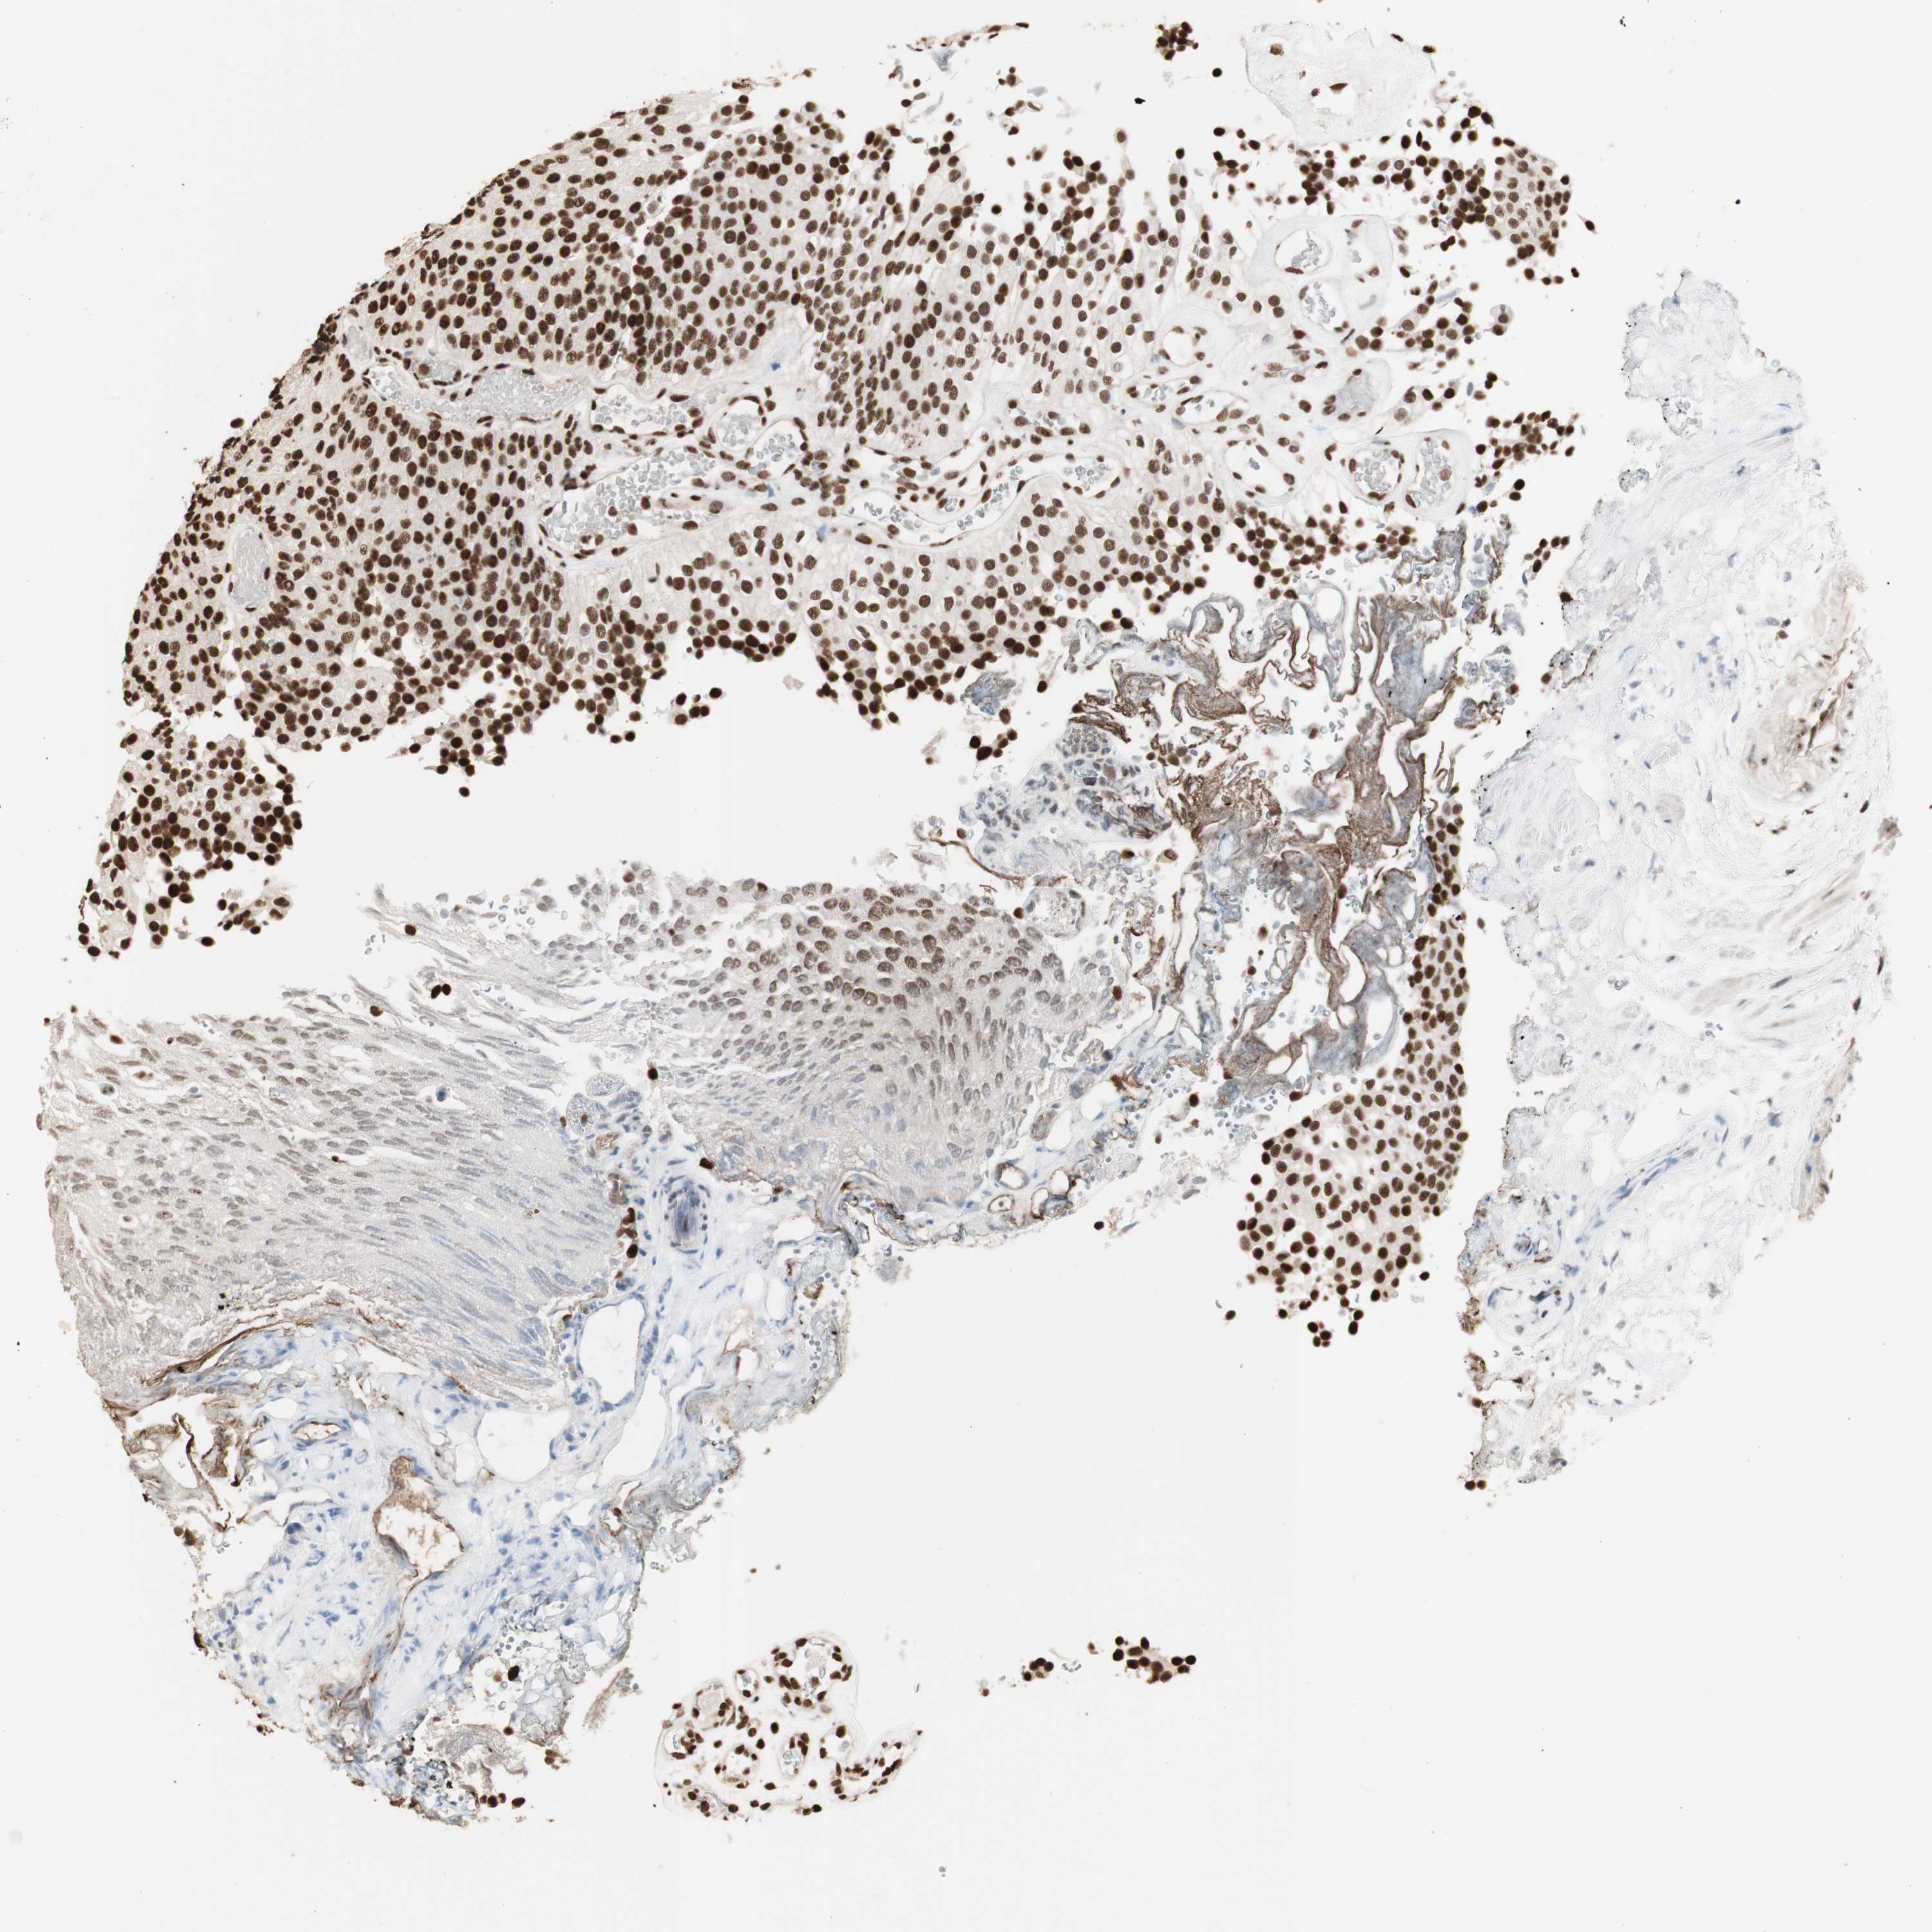

UROTHELIAL CANCER - Protein expressioni

A mouse-over function shows sample information and annotation data. Click on an image to view it in a full screen mode. Samples can be filtered based on level of antibody staining by selecting one or several of the following categories: high, medium, low and not detected. The assay and annotation is described here.

Note that samples used for immunohistochemistry by the Human Protein Atlas do not correspond to samples in the TCGA dataset.

Antibody stainingi

Antibody staining in the annotated cell types in the current human tissue is reported as not detected, low, medium, or high, based on conventional immunohistochemistry profiling in selected tissues. This score is based on the combination of the staining intensity and fraction of stained cells.

Each image is clickable and will lead to virtual microscopy that enables deeper exploration of all samples and also displays staining intensity scores, fraction scores and subcellular localization as well as patient and tissue information for each sample.

Antibody HPA001666

Antibody CAB012403

Staining

High

Medium

Low

Not detected

Intensity

Strong

Moderate

Weak

Negative

Quantity

>75%

75%-25%

<25%

None

Location

Nuclear

Cytoplasmic/membranous

Cytoplasmic/membranous,nuclear

Urothelial carcinoma, High grade

Urothelial carcinoma, Low grade

Adenocarcinoma, NOS